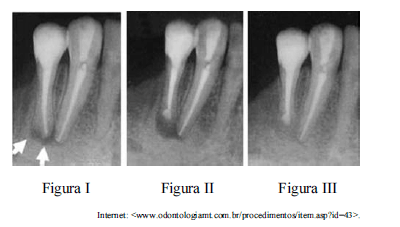

Um paciente do sexo masculino, de quarenta e seis anos de idade, procurou atendimento odontológico por motivo de presença de fístula recorrente, havia seis meses, na região anterior inferior. O paciente relatou, ainda, ter tratado canal nos elementos 43 e 44 havia cerca de dez anos.

Considerando as imagens radiográficas como referência, nas quais as setas indicam presença de alteração periapical, julgue os itens subsecutivos a respeito do caso clínico apresentado.